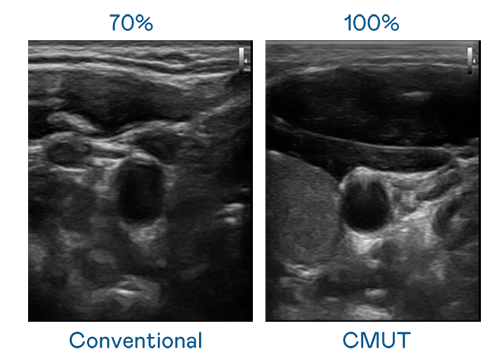

CMUT 技術是一種用電容式微機電元件來產生超音波訊號的技術。與傳統 PZT 壓電式技術相比,CMUT 頻寬增加 30%,更寬頻的超音波訊號讓影像解析度大幅提升,是實現高影像品質醫療超音波掃描、促進精準醫療發展的關鍵技術。

超音波影像的解析度高低,首先取決於探頭能發出的訊號頻寬。8868体育 CMUT 可提供高清晰的超音波訊號,提供高頻寬、高靈敏度、影像紋理細節更高的超音波影像,協助醫護人員縮短影像判讀時間及利用精準的醫療影像進行診斷。